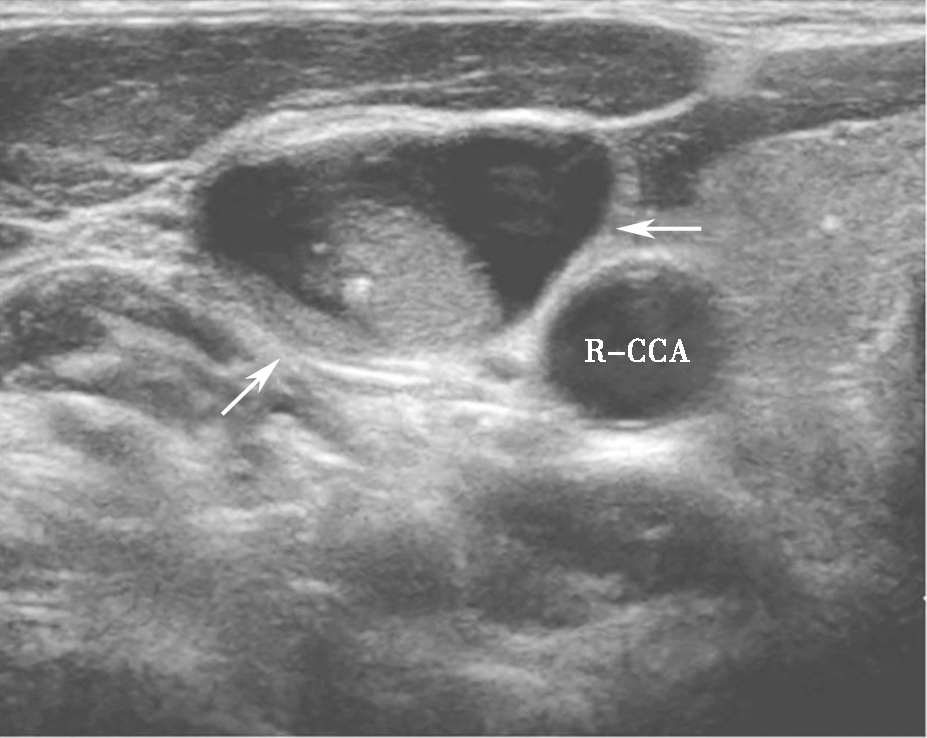

(六)亚急性甲状腺性炎

亚急性甲状腺炎超声表现为腺体内片状低回声,边界模糊,内可有散在的稍强点状回声,探头挤压时有压痛(图5)。低回声以外腺体彩色多普勒血流信号基本正常,低回声内部血流信号轻度增加或无明显增加,周边无明显血管绕行,部分低回声内部可显示正常甲状腺血管穿行。患者可伴有颈淋巴结增大。

图5颈部正中偏右侧横切面:甲状腺右叶饱满,可见片状低回声,边界模糊(箭头所示)R-CCA:右侧颈总动脉,T:气管